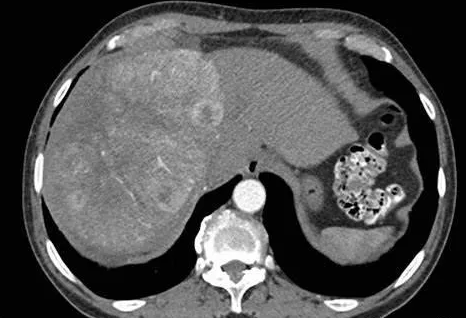

筛查手段最好的是影像学,目前阶段我国主要是依靠B超 AFP的方法,但绝对不可单独使用AFP。

image.png

有条件的情况下也可以使用MRI增强扫描,无电离辐射,能够发现足够小的肝癌,甚至对于癌前病变,比如肝硬化结节,退变结节等进行追踪和评估,而且可做到一站式检查,定位,定性,术前评估等。